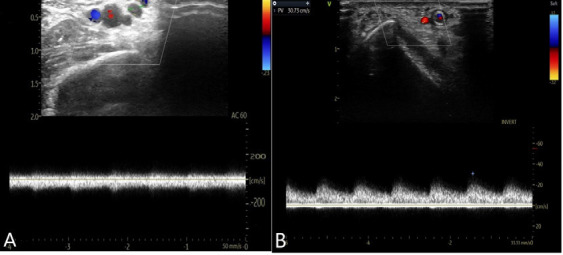

桡动脉动静脉瘘(AVF)在桡动脉介入治疗后极为罕见。在这里,我们报告一个73岁的男性病例,他因急性心肌缺血综合征入院,并接受了左前降支和旋支近端经桡动脉血管成形术。14个月后,患者表现为进行性肿胀,浅表静脉扩张,可触及的震颤,持续的摩擦和局部刺痛。多普勒超声(DUS)诊断桡骨AVF伴多瘘性交通引流至头静脉,经对比增强计算机断层扫描(CECT)证实。尝试使用长时间压缩绷带(bbb12小时)和DUS探头进行局部压缩,但仍然无效。将2.8 × 26 mm Graftmaster支架(Abbott Vascular, USA)经肱入路置于桡动脉瘘颈处,在12 atm压力下缓慢扩张60秒,并在15 atm压力下用3 × 15 mm非顺应性球囊进行扩张。术后血管造影显示瘘完全闭合,掌弓灌注恢复。这是首次报道的使用覆盖支架经肱入路成功排除RAVF的病例,也是第二次使用支架移植经皮排除RAVF的病例。

Radial arteriovenous fistula (AVF) following radial intervention is exceedingly scarce. Here, we report a case of a 73-year-old man who was admitted with acute myocardial ischaemic syndrome and underwent transradial angioplasty of the proximal left anterior descending and circumflex artery. Fourteen months later, he presented with progressive swelling, dilated superficial veins, a palpable thrill, continuous bruit, and tingling at the local site. Doppler ultrasonography (DUS) diagnosed radial AVF with multiple fistulous communications draining into the cephalic vein, confirmed by contrast-enhanced computed tomography (CECT). Local compression using a prolonged compressive bandage (>12 hours) and a DUS probe was attempted but remained ineffectual. A 2.8 × 26 mm Graftmaster stent graft (Abbott Vascular, USA) was deployed into the radial artery across the fistula neck via a transbrachial approach, slowly expanded over 60 seconds at 12 atm pressure, and post-dilated with a 3 × 15 mm noncompliant balloon at 15 atm pressure. A post-procedure angiogram displayed complete closure of the fistula with restoration of palmar arch perfusion. This is the first reported case of successful exclusion of RAVF through transbrachial approach using a ever covered stent, and only the second case overall of percutaneous exclusion using a stent graft.